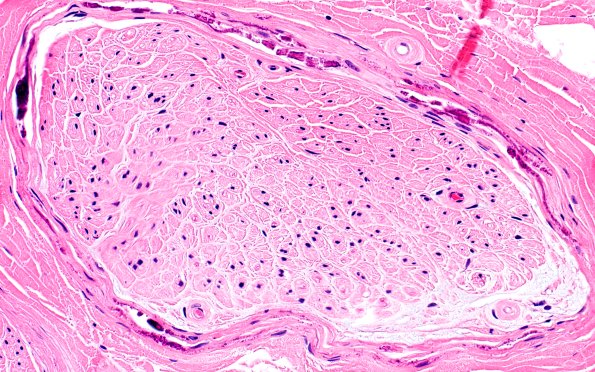

6A3 (Case 6) H&E 40X 3

There are frequent prominent perineurial calcifications but no evidence of vasculitis or inflammation.